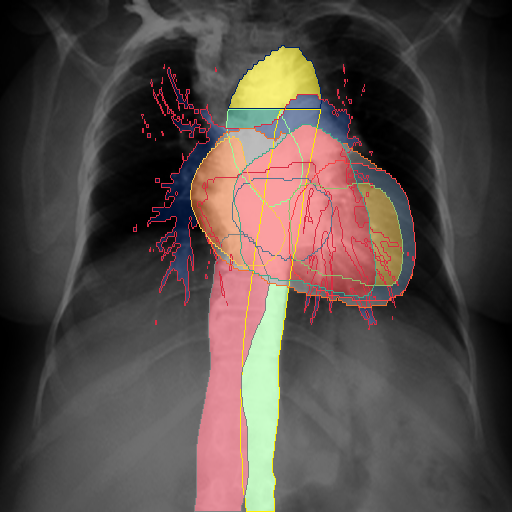

We display qualitative results in Fig. 3. The annotators tend to be content with most annotations. There are edits at the extensions of the esophagus, trachea, and aorta and corrections of the lower ribs. There is little consensus for classes in the abdominal area, such as the stomach, as seen on the right of Fig. 3 . In contrast, the annotators often align for bone classes.

We show the quantitative segmentation performance against medical expert annotations for all classes in Fig. 3 . The dashed lines represent the IAA, whereas the dotted line displays the average MAA. As the task for the human annotators was not to annotate from scratch but to correct wrong pixel-wise predictions, we can see a high MAA for most classes. In the frontal view, the most significant disagreements exist for rare bone structures such as L3 and C4, lower ribs, the mediastinal distribution, or the breast tissue. The IAA and MAA are highly similar with mIoU of respective 95% and 94%. The Hausdorff distance for MAA is slightly lower than the IAA, indicating slight differences in boundary annotations while maintaining a considerable overlap with the other annotator. In the lateral view, the concrete delineation of rib structures appears ambiguous, leading to lower MAA and IAA with a greater IAA than MAA for all metrics in this supercategory. Overall there is less agreement between the medical experts in the lateral view, leading to a better average MAA than IAA across all metrics (i.e. 85% vs 83% mIoU). While the experts propose changes to the original predictions, they are often not overlapping. In the lateral view, rib segmentations can become quite hard to interpret. While both annotators disagree with the rib segmentations, they do not always agree on how they should look. Similarly to the frontal view, tube-like structures like the esophagus are extended as they can appear fractured at times.